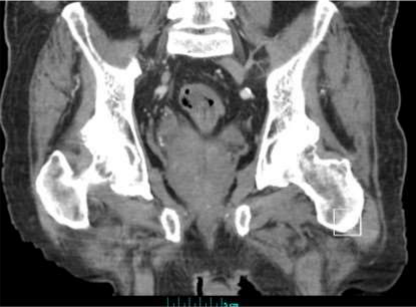

Figure A showing the 7x5 cm lipoma with coloanal intussusception.

An 81-year-old man with history of coronary artery disease on Plavix presented with a large mass protruding from his anus. The patient was straining during defecation and felt severe abdominal and rectal pain. Vital signs and labs were normal. Physical examination revealed left lower quadrant tenderness, and a large mass protruding through his anus. Computed tomography (CT) scan of the abdomen and pelvis revealed a prolapsed 7x5cm sigmoid lipoma with coloanal intussusception, without evidence of obstruction, perforation, or peritonitis (figure A). Attempts to reduce the lipoma manually at bedside were unsuccessful, therefore the patient was taken for emergent resection. The gastrointestinal team was asked to assist so that direct visualization could be used to resect the lipoma stalk. A pediatric colonoscope was inserted alongside the lipoma into the rectum revealing a large stalk of prolapsed colon extending to 20cm from the anal verge (figure B). The retroflexion view showed the stalk traversing the anus surrounded by large hemorrhoids (figure C). The colonoscope could not be advanced past the stalk due to intussusception from the lipoma stalk pulling the colon forwards. Endoloops and a LigaSure device were used to transect the lipoma since the patient was on Plavix and had a high bleeding risk. Using the colonoscope for constant visualization, two Endoloops were placed manually to 10cm from the anal verge using caution to avoid anchoring onto the colonic wall. A third Endoloop was placed at the junction of the lipoma and its stalk at the anal verge. The colonoscope was removed and an Impact LigaSure device was used to slowly transect across the apex of the lesion right at the anal verge with manual pressure to retract the skin, perianal region, rectal mucosa, and hemorrhoids from the LigaSure device (figure D). The colonoscope was then reinserted and the colon was easily traversed up to 40 cm from the anal verge. The stalk was noted to have the two Endoloops in place without bleeding. Pathology revealed a submucosal lipoma with acute inflammation and partial fat necrosis as well as overlying colonic mucosa with ulceration (figure E).

Diagnosis can be made with colonoscopy, barium radiographs, endoscopic ultrasound (EUS), confocal laser microscopy (CLE), or CT scan. Colonic lipomas appear as yellowish smooth submucosal lesions on colonoscopy. Characteristic features include, “cushion or pillow sign” which is a flattening/indentation of the tissue when pushing the biopsy forceps against the lipoma and restoration of its regular shape once the forceps are removed; “naked fat sign” which is when fatty tissues extrudes through the biopsy site; and “tent-sign” which is when the mucosa is grasped with forceps and pulled upwards creating a tent shape 7. Limitations of colonoscopy include reduced sensitivity for diagnosing atypical lipomas with necrosis or ulceration 7. Additionally, biopsies obtained during colonoscopy may fail to obtain adequate adipose tissue needed to make the diagnosis 4. CT scan is currently the imaging study of choice. Lipomas appear as well defined, ovoid, intramural lesions with a greasy density. CT is specifically useful when lipomas are > 2cm and in those with associated complications such as intussusception, necrosis or infarction 4,6,7,10,17. Barium radiography is sensitive but not specific, and EUS is useful for diagnosing atypical appearing lipomas 7,10,17.